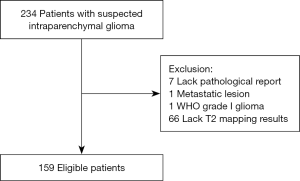

Initial eligibility screening identified 234 patients with suspected glioma. There were 66 patients excluded due to lack of T2 mapping results and a further 7 excluded for the absence of a post-operative pathological report. One patient with lung cancer metastases and one patient with pilocytic astrocytoma were also excluded. A total of 159 patients with confirmed diffuse gliomas were recruited for the study. Figure 1 is a summary flow diagram of patient selection. The interval between radiological imaging and surgery was less than one week.